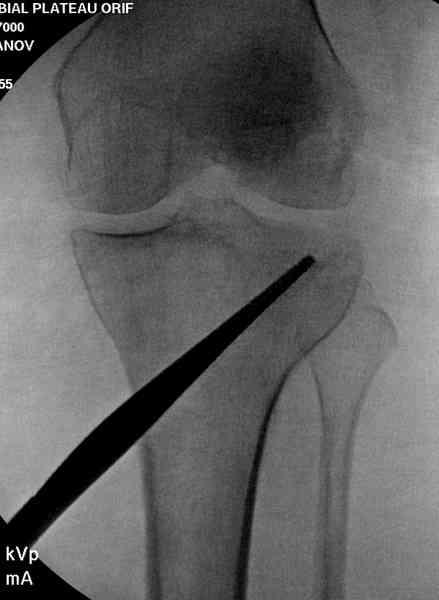

Медиально, обычно на протовоположной

строне, делается окно в кортикальном слое, кривым забойником под рентгеном поднимается импрессия.

После заполнения образовавшейся полости в метафизе

кортикальное окно можно прикрыть.

Это техника применяется, когда имеется

центральная импрессия, а при ипрессии с краевым переломом - после приподнимания импрессии опорная (Butress) пластина, как на снимке.